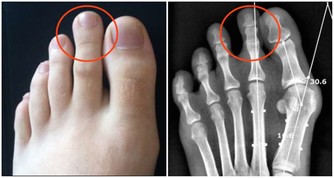

③跟骨頭搶鈣

吃鹽過多,需要排掉的鈉就越多,此時鈣的消耗也就越大,從而加速鈣流失、骨質流失;

長期過量吃糖,會帶來這些危害:傷牙、長胖、跟骨頭搶鈣、加速皮膚老化、誘發多種疾病(痛風、糖尿病、心腦血管等慢性病)。